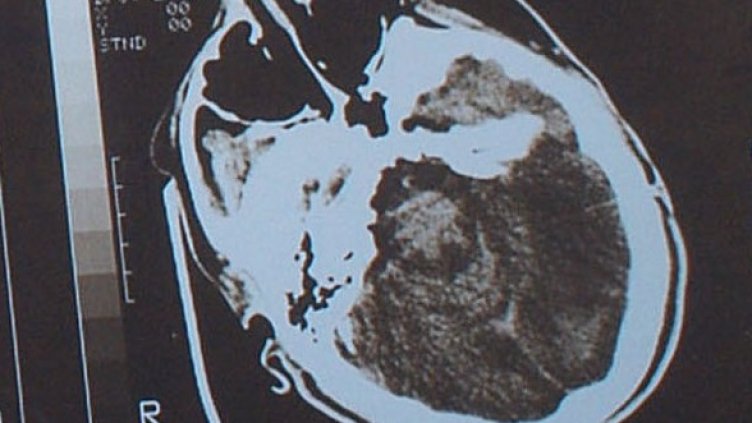

След това подложили групата на изследване с магнитен резонанс. Оказало се, че тестваните с проблеми в концентрацията имат по-голям обем сиво вещество в левия горен париетален лоб (ГПЛ).

Екипът на д-р Канай предполага, че когато хората съзряват, сивото им вещество се насища с неврони, така че мозъкът да работи по-ефективно. Колкото по-голям обем сиво вещество имат, толкова по-незрял е техният мозък. Ето защо децата по-лесно се разсейват, отколкото възрастните.